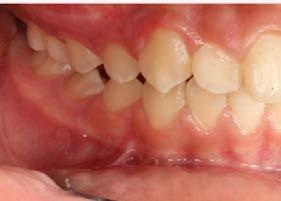

Introducción: La maloclusión clase II provoca proporciones irregulares en el perfil facial. Puede deberse a un maxilar adelantado y a incisivos superiores proinclinados y protruidos. Esta condición puede corregirse mediante el uso de aparatos ortopédicos en pacientes en crecimiento.

Objetivos: Conseguir clase I canina, controlar el crecimiento vertical, disminuir la convexidad esqueletal, reducir la sobremordida horizontal y mejorar el perfil facial. Caso clínico: Paciente femenina de 9 años, clase II esqueletal, biotipo dolicofacial, perfil convexo, clase II molar, clase II canina y proinclinación de incisivos superiores e inferiores. Resultados: Se logró clase I canina, se controló el crecimiento vertical, se redujo la convexidad esqueletal, se mejoró la sobremordida horizontal y el perfil facial. Conclusiones: El uso combinado de aparatos ortopédicos y aparatología fija en pacientes en crecimiento, junto con un diagnóstico y plan de tratamiento acertado, permite obtener resultados exitosos y estables en la corrección de estas maloclusiones.

La relación maxilomandibular desempeña un papel importante en la posición de los molares y puede clasificarse como clase I, II o III, de acuerdo con la clasificación de Angle. Esqueletalmente, esta relación solo puede determinarse mediante estudios radiológicos; los modelos de estudio solo ofrecen una aproximación clínica.1